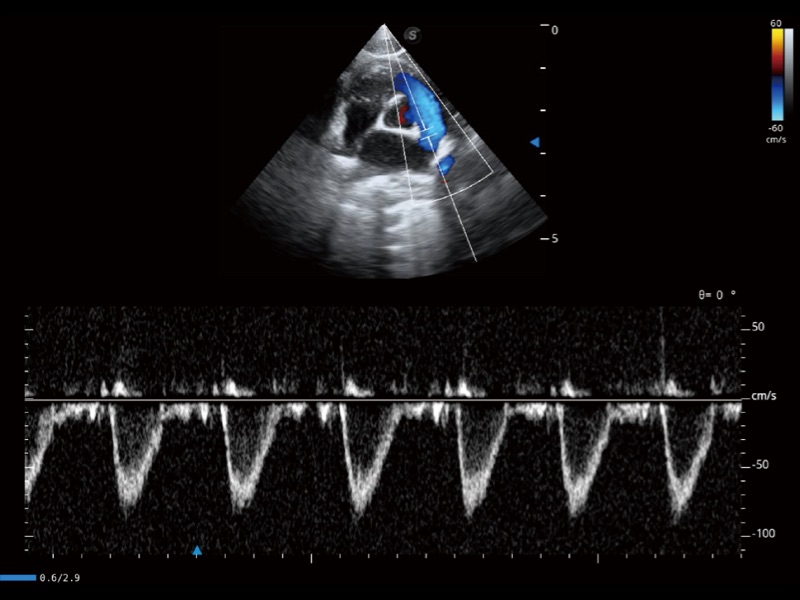

(猫)肺动脉血流频谱

(犬)左室长轴血流